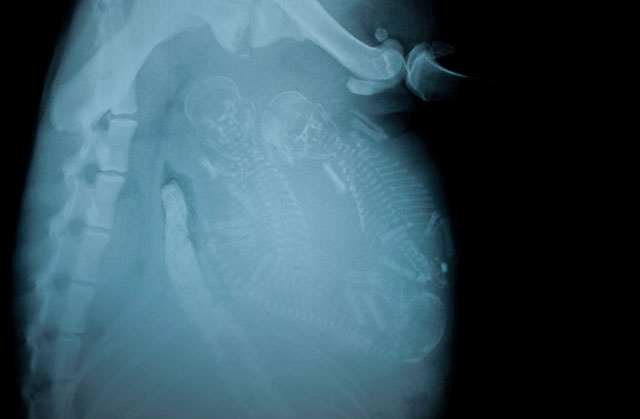

İnsanların ultrason görüntülerini görmeye hepimiz alışkınız. Ancak hamile hayvanların ultrason görüntüleri sizleri çok şaşırtacak.Kaplumbağa

İnsanların ultrason görüntülerini görmeye hepimiz alışkınız. Ancak hamile hayvanların ultrason görüntüleri sizleri çok şaşırtacak.